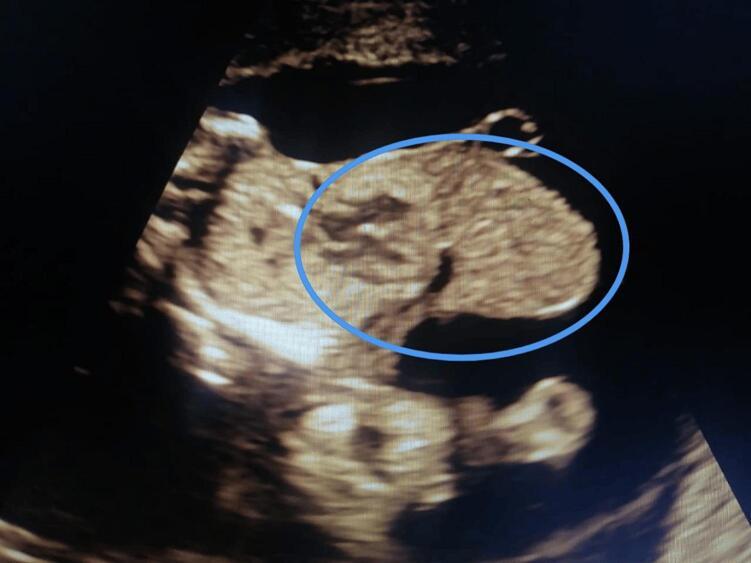

In case 1, a routine antenatal scan at 12 weeks' gestation revealed thoracoabdominal ectopia cordis in a 29-year-old woman. The pregnancy was terminated medically due to the severity of the anomalies and the poor prognosis. A 32-year-old patient in case 2 had a diaphragmatic hernia, thoracoabdominal ectopia cordis and midline abdominal wall abnormalities. After counselling, a medical termination was chosen. The ultra-sonographic features were confirmed by autopsy results in 2 cases.

Early diagnosis is feasible in the first trimester if ectopia cordis and omphalocele exist. Additionally, development in ultrasound technology provides us with better visualization and early diagnosis. With patients who have fully developed Cantrell syndrome and those who also have accompanying anomalies, the prognosis is often poor, with short survival and quality of life.

在病例1中,一名29岁女性在妊娠12周时进行的常规产前扫描显示胸腹型心脏异位。由于异常严重且预后不良,该妊娠通过药物终止。病例2中的一名32岁患者患有膈疝、胸腹型心脏异位和中线腹壁异常。经过咨询后,选择了药物流产。这2例的超声特征均经尸检结果证实。

如果存在心脏异位和脐膨出,在孕早期进行早期诊断是可行的。此外,超声技术的发展为我们提供了更好的可视化和早期诊断。对于患有完全型坎特雷尔综合征以及伴有其他异常的患者,预后通常较差,生存期短且生活质量低。